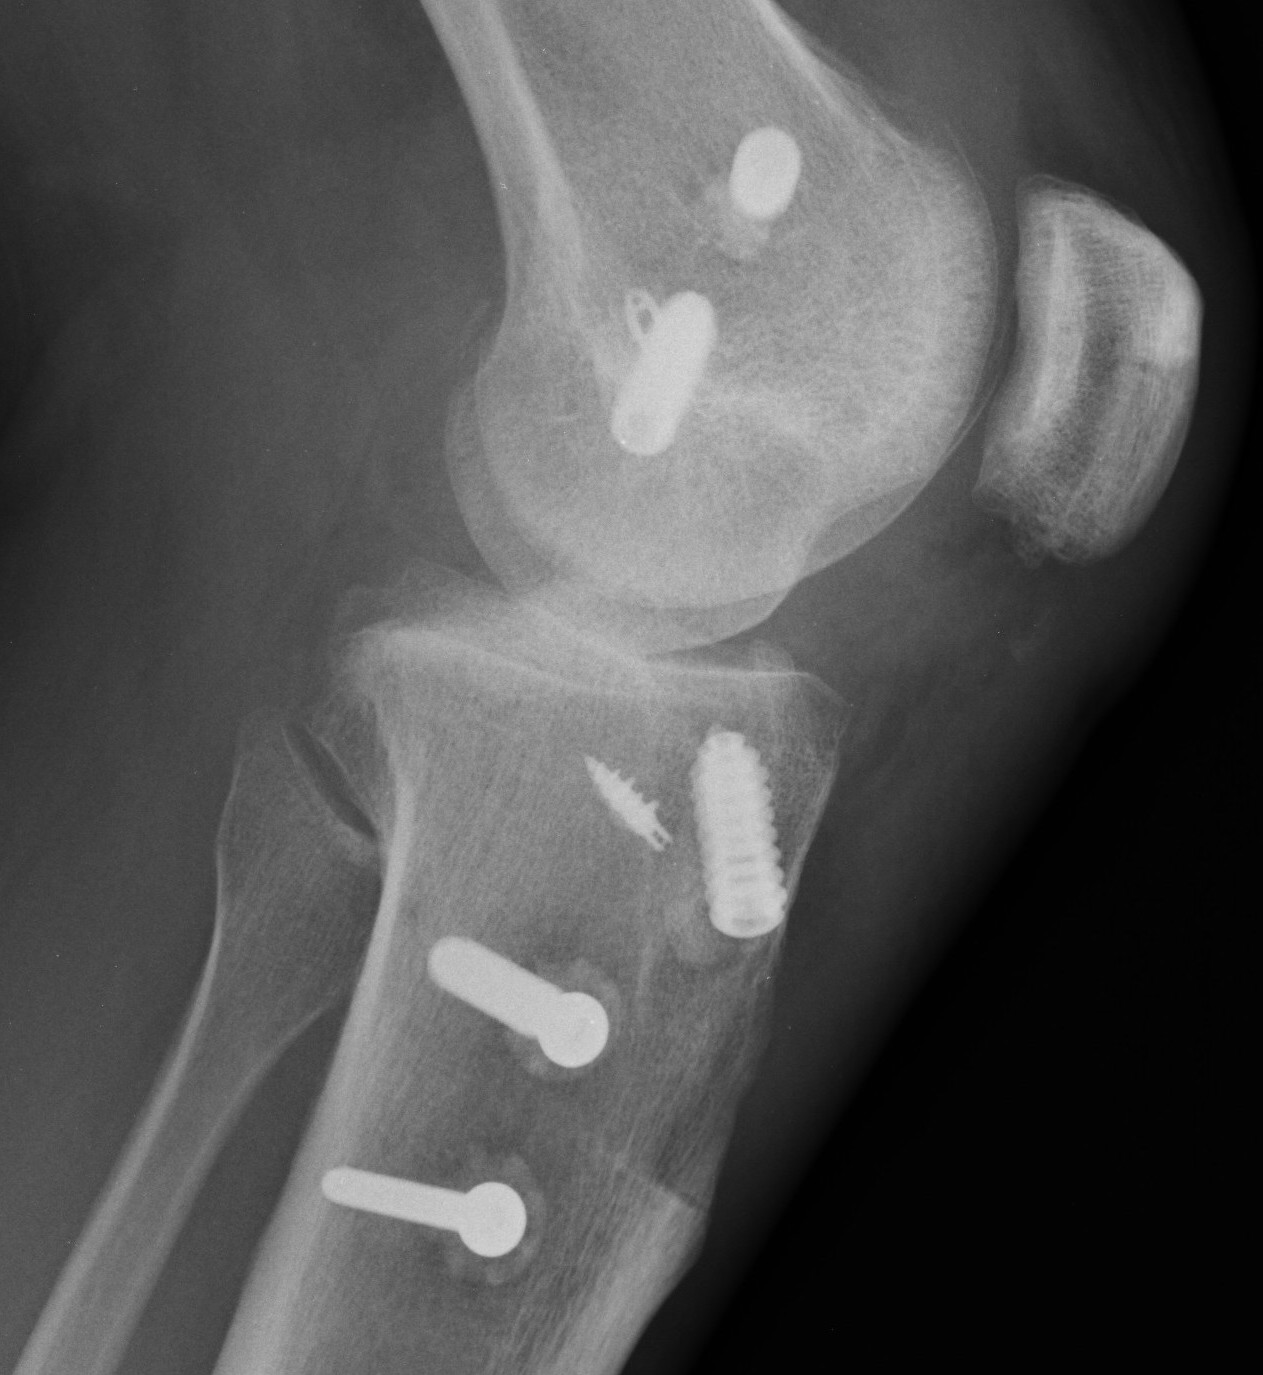

Bony MCL Avulsion

Elevate VMO and repair with staples or screw

Advancement of proximal MCL / POL with screw, and imbrication / tightening of POL

Tightening of proximal MCL / POL with sutures

Advancement of femoral MCL and staple / suture anchor fixation

3. Reconstruction of MCL and posteromedial corner

A. Single bundle anatomic allograft MCL reconstruction (no POL)

Femoral attachment

- 4 mm proximal and posterior to medial epicondyle

- image intensifier: intersection of the posterior femoral condyle with Blumensaat's line

- 40o anterior to avoid notch

- 40o proximal to avoid PCL tunnel

Tibial attachment

- 6 cm from joint line

- just posterior to pes attachment

C. Double bundle anatomic reconstruction of MCL and POL